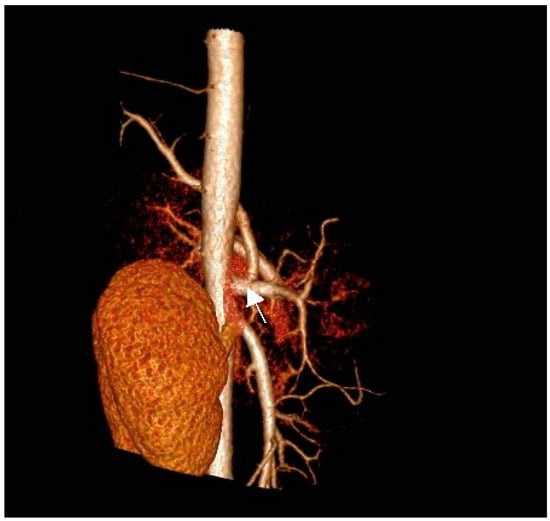

There was no communication of the affected lung parenchyma with bronchi of the left inferior lobe. We noted no further infiltrative changes in the remainder of the left and right lungs. Contrast-enhanced CT scanning with 3D reconstruction showed normal configuration of the thoraco-abdominal aorta, celiac trunk, and renal arteries. The celiac trunk originated from the abdominal aorta at the level of the intervertebral space Th12-L1. The systemic feeding artery (proximal diameter of 5 mm) originated from the celiac trunk. This artery supplied the pulmonary intralobar sequestration in the inferior lobe of the left lung (Figure 2a,b).

Figure 2.

(a) Contrast-enhanced CT scan of the thoraco-abdominal aorta with 3D reconstruction of aorta, celiac trunk, and renal arteries. Note the feeding artery (indicated by arrow) with a diameter of 5 mm supplying the sequestration in the inferior lobe of the left lung (antero-posterior [AP] view). (b) Anomalous artery arising from the celiac trunk (artery indicated by arrow; lateral view).